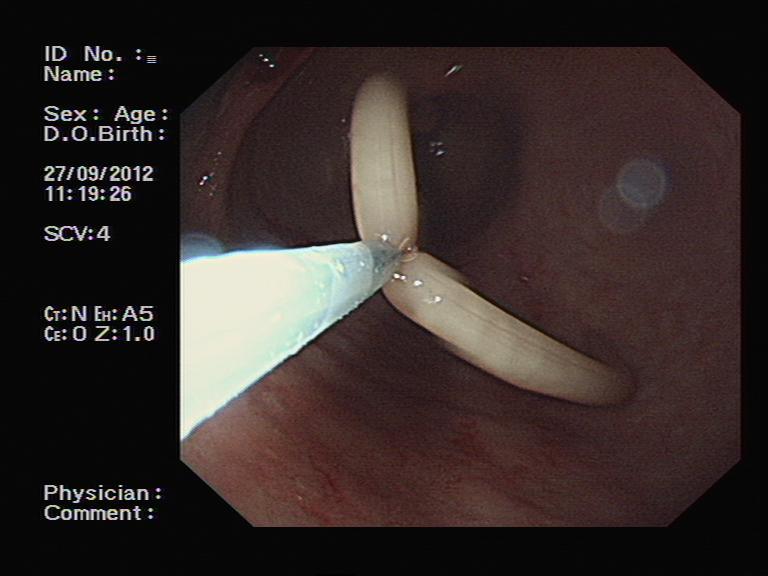

胃镜检查证实了胃角部位的一处不大的溃疡,我们再次进行了活检。不过,意想不到的是,当检查医师进镜至十二指肠时,吃惊地发现十二指肠球部有一个正在蠕动的白色圆柱状物体,这是什么呢?原来是一条蛔虫,头端还在十二指肠降部,尾端留在了球部。见状,蔺武主任医师反复尝试,最终用圈套器取出了蛔虫。患者家属很高兴,因为找到了腹痛的原因,那么,事情结束了吗?检查之后病理很快回报:患者的胃溃疡活检标本中存在局部癌变,该患者的胃角溃疡为早期胃癌。

圈套器取出蛔虫